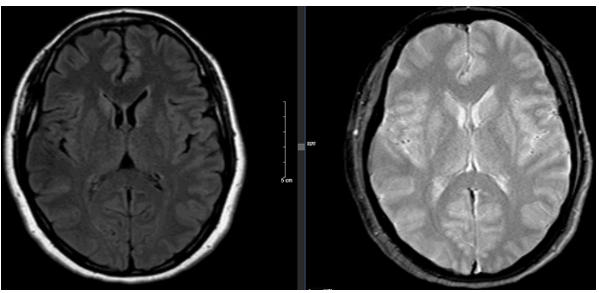

- Cộng hưởng từ sọ não (trước mổ): Hiện không phát hiện tổn thương nghi ngờ thứ phát.

Hình 3: Hình ảnh chụp cộng hưởng từ sọ não không phát hiện di căn